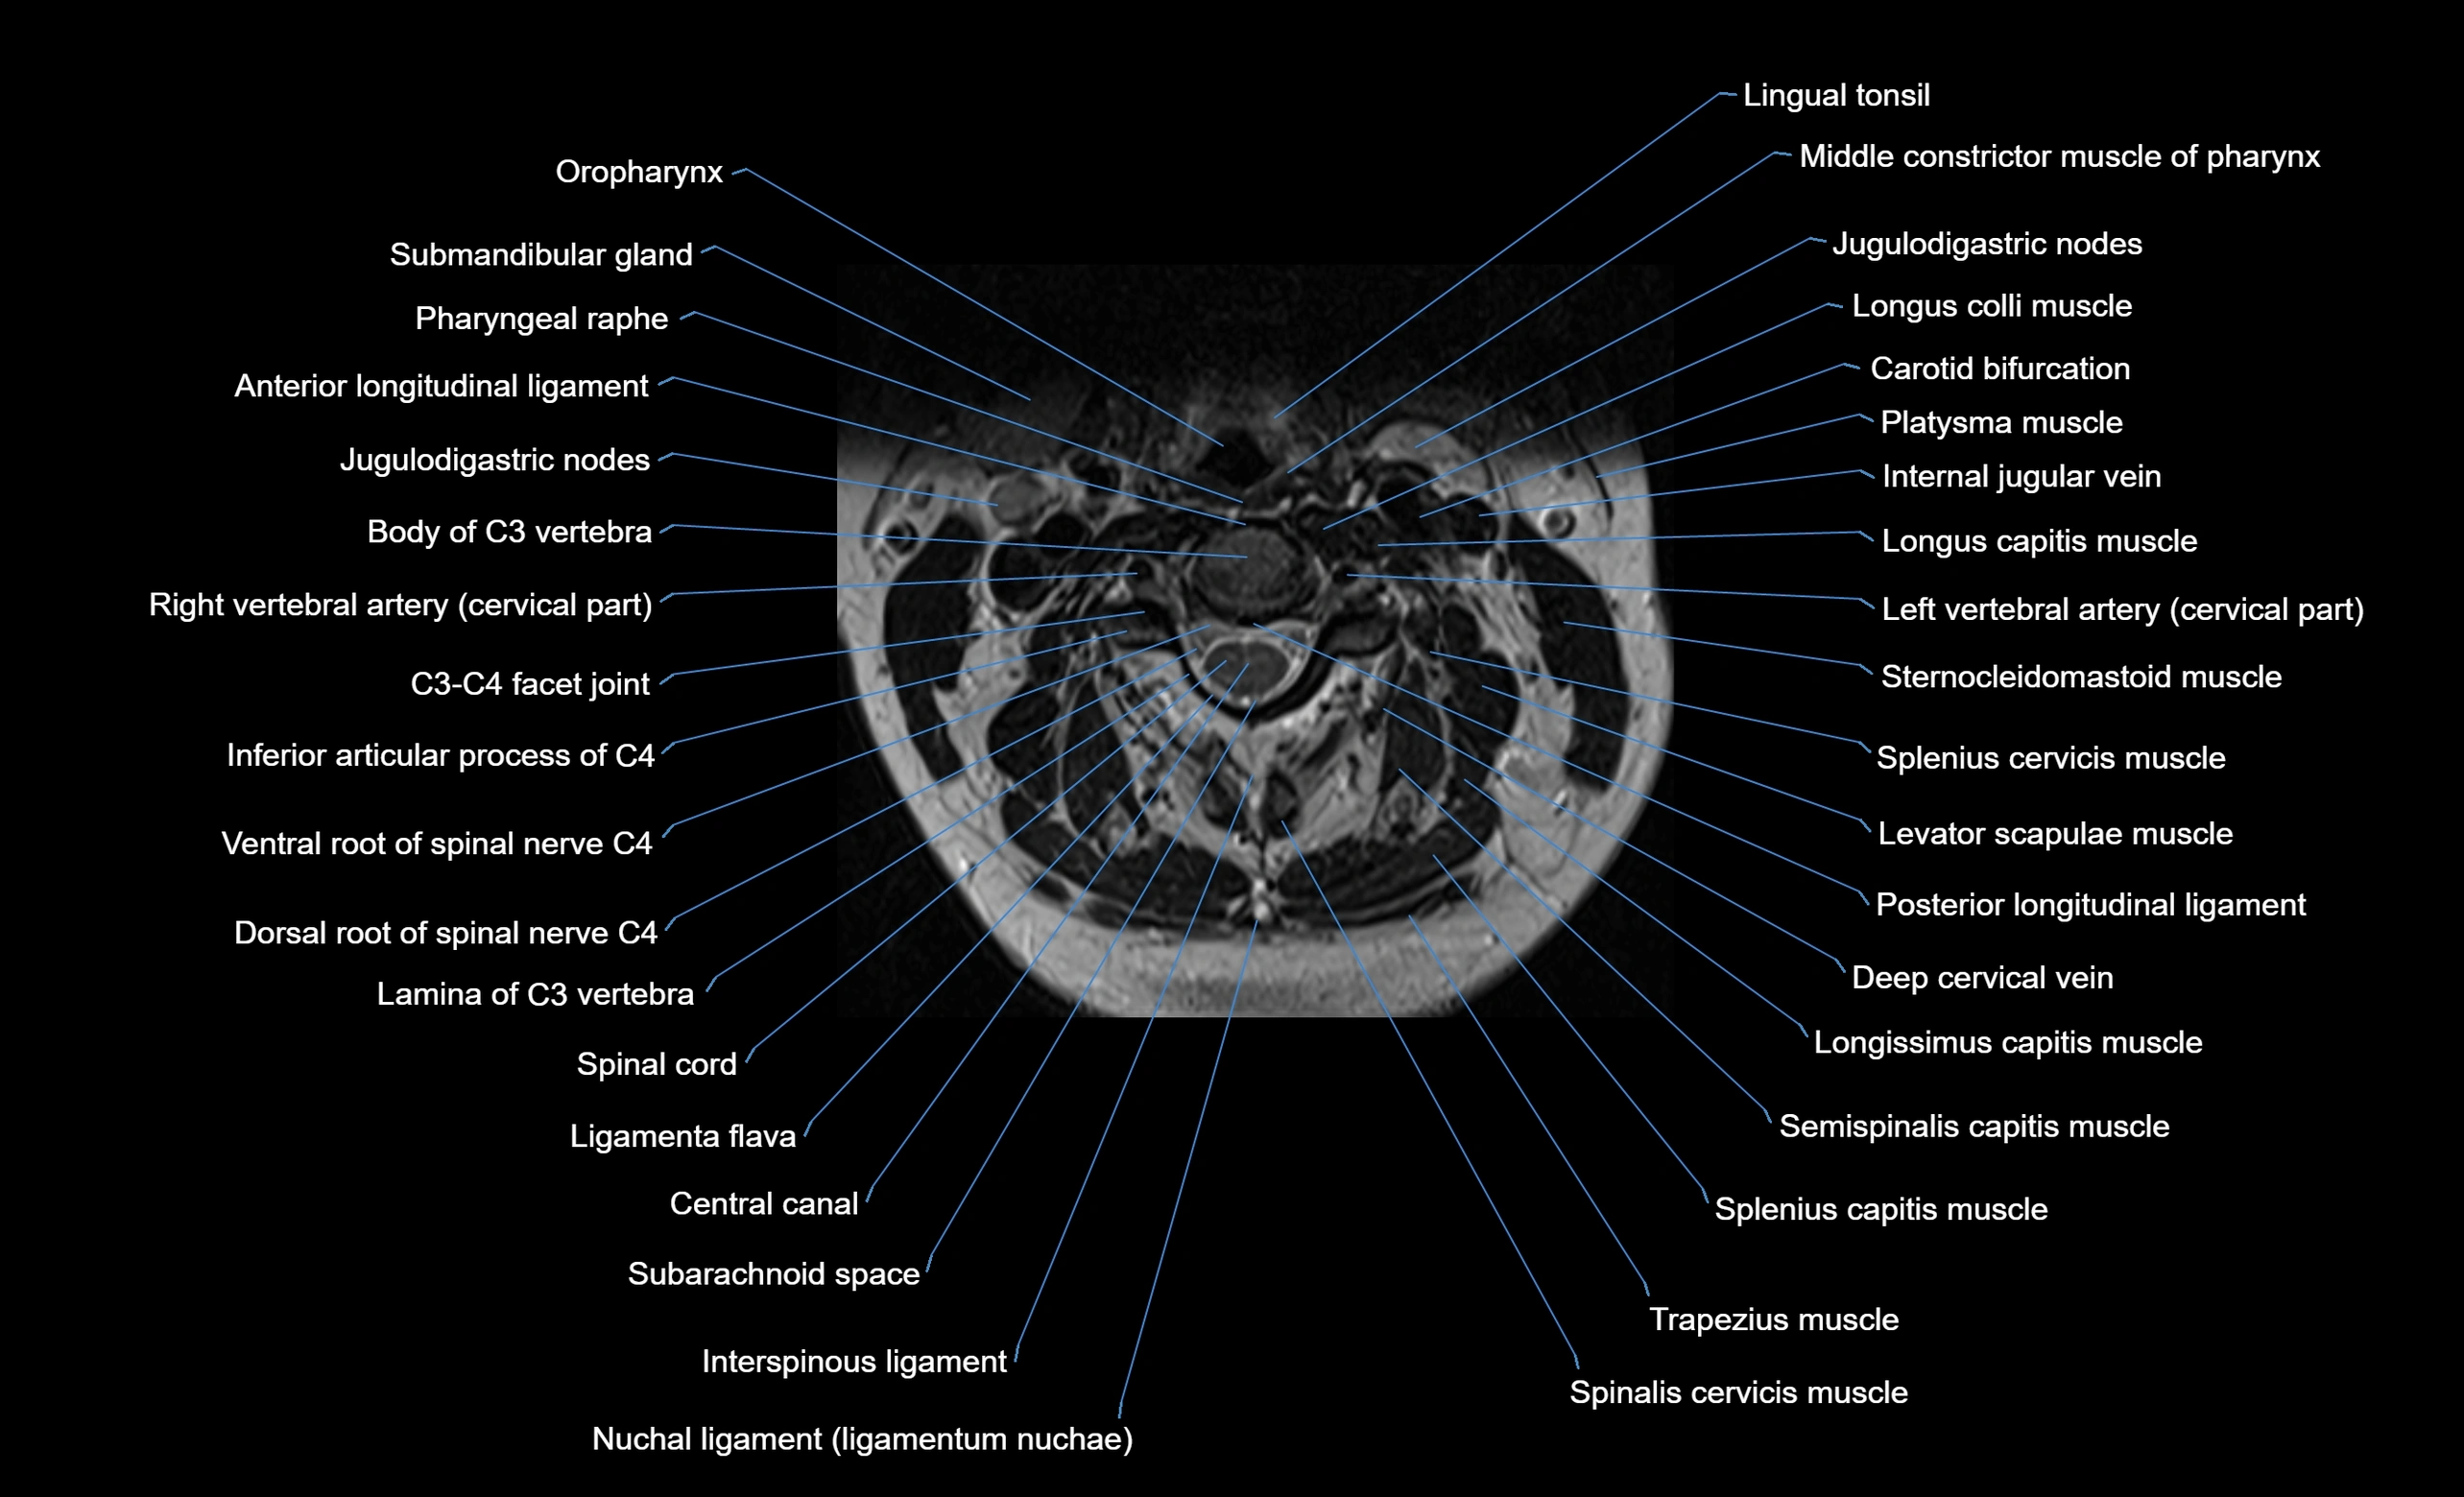

MRI image

image